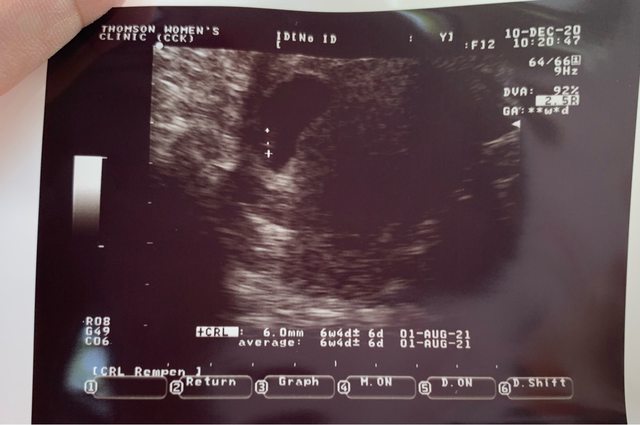

第一次給醫生看的時候 他說有可能有宮外孕的機率 如果這幾天有肚子痛什麼的再回診 8/19 二週後回診 今天有照超音波+內診 因為這超音波時,醫生說我子宮有點後頃 沒有照到東西 就換宮內診 照出來胚囊7w+2d,胚囊變大大概3公分 醫生宮內診有照到卵黃囊,但是沒有心跳 醫生看完後覺得我蠻大的機率是胚胎有問題 第一胎因為在國外生的 那時候也都沒什麼問題 第一次遇到醫生這樣說 整個驚嚇到 要我一週後再回診 說這週有可能會自然流掉 大概跟我說可能遇到的情況 注意有沒有大出血 如果沒有 可能就要安排手術了 今天照的照片忘記拿 有點被嚇到恍神 請問大概需要等幾週在決定要不要手術呢? 我打算週五再掛別的醫院的醫生確認一下 附上第一胎6w的照片 https://i.imgur.com/qlJ5n0e.jpeg